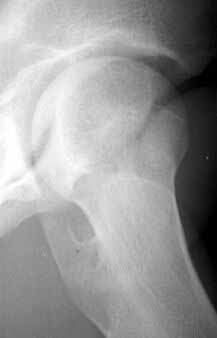

Here are some pictures from a case where the femoral head was surgically dislocated and trimmed for acetabular and femur impingment syndrome.

The technique is described by Ganz and Mast as a digastric approach (trochanter flip osteotomy) to the hip joint without destroying blood supply to the femoral head. The approach may also be applied to some acetabular fractures.